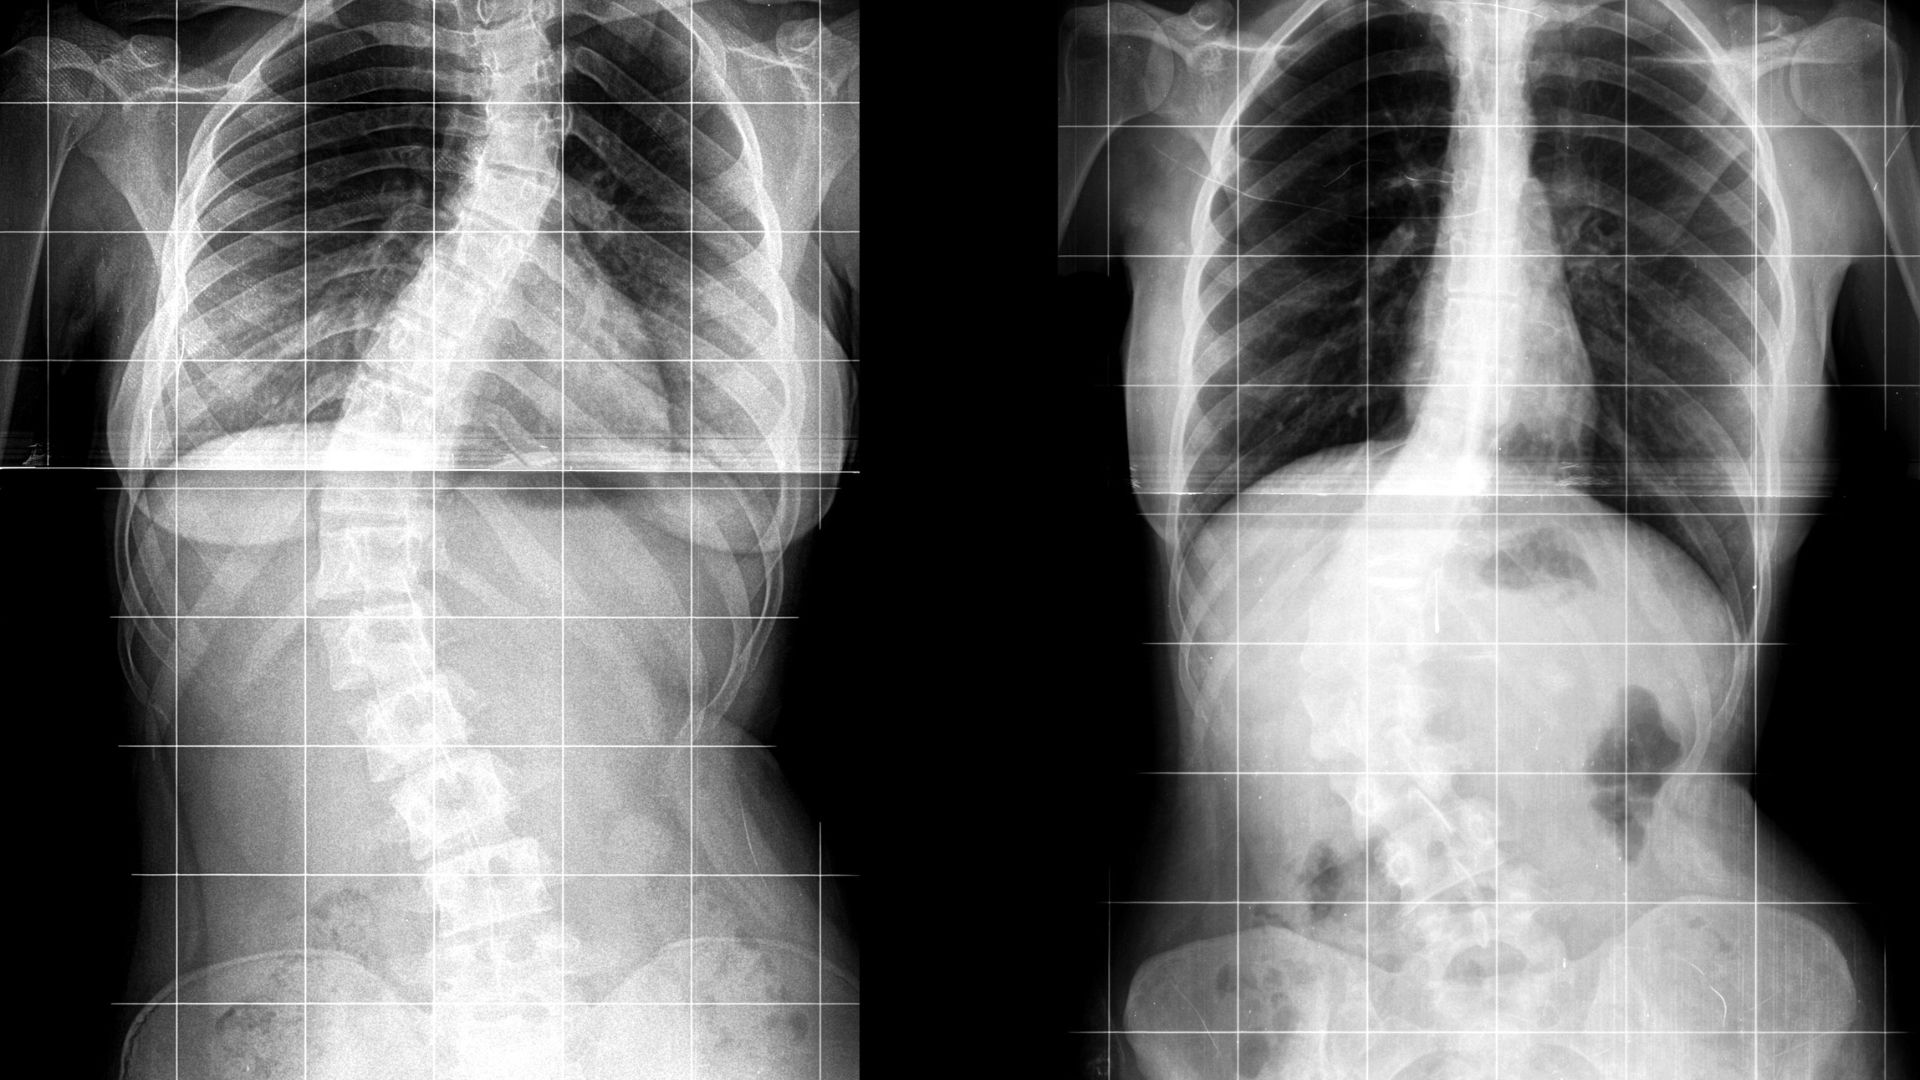

Trong chẩn đoán bệnh lý cột sống, mỗi phương pháp hình ảnh đều có vai trò riêng. X-quang thường được sử dụng để khảo sát cấu trúc xương, đánh giá tình trạng gãy, trượt hoặc cong vẹo cột sống. Tuy nhiên, X-quang không cho thấy được đĩa đệm và rễ thần kinh nên không đủ để chẩn đoán thoát vị đĩa đệm.

MRI không sử dụng tia X, cho phép quan sát rõ mô mềm và cấu trúc thần kinh. Đây là lý do phương pháp này được đánh giá cao trong chẩn đoán các bệnh lý liên quan đến đĩa đệm. Việc lựa chọn phương pháp nào sẽ phụ thuộc vào tình trạng cụ thể của người bệnh và mục tiêu chẩn đoán, nhưng trong trường hợp nghi ngờ thoát vị đĩa đệm, MRI thường mang lại thông tin đầy đủ và giá trị nhất.